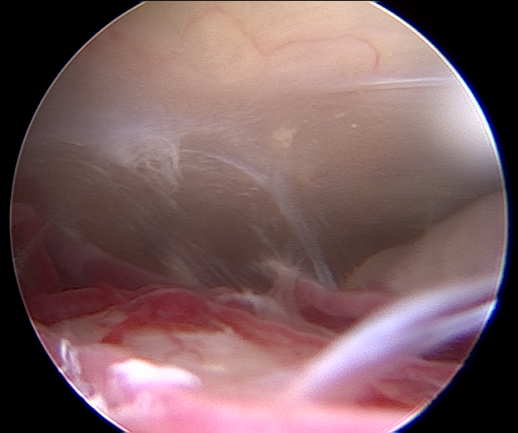

Μία από τις πιο συνηθισμένες παθήσεις στο κρανίο στην οποία χρησιμοποιείται το ενδοσκόπιο είναι οι όγκοι του τουρκικού εφιππίου, όπως τα καλοήθη αδενώματα της υπόφυσης και τα κρανιοφαρυγγιώματα. Στις περιπτώσεις αυτές η είσοδος στο κρανίο γίνεται από την μύτη (Εικ. 6). Το ενδοσκόπιο παρέχει εξαιρετική απεικόνιση της περιοχής από τον βλεννογόνο της μύτης μέχρι και τον σφηνοειδή κόλπο και την περιοχή της υπόφυσης μετά το άνοιγμα του εδάφους του τουρκικού εφιππίου. Αντιπροσωπευτικές διεγχειρητικές φωτογραφίες φαίνονται στις εικόνες 8α,β,γ.